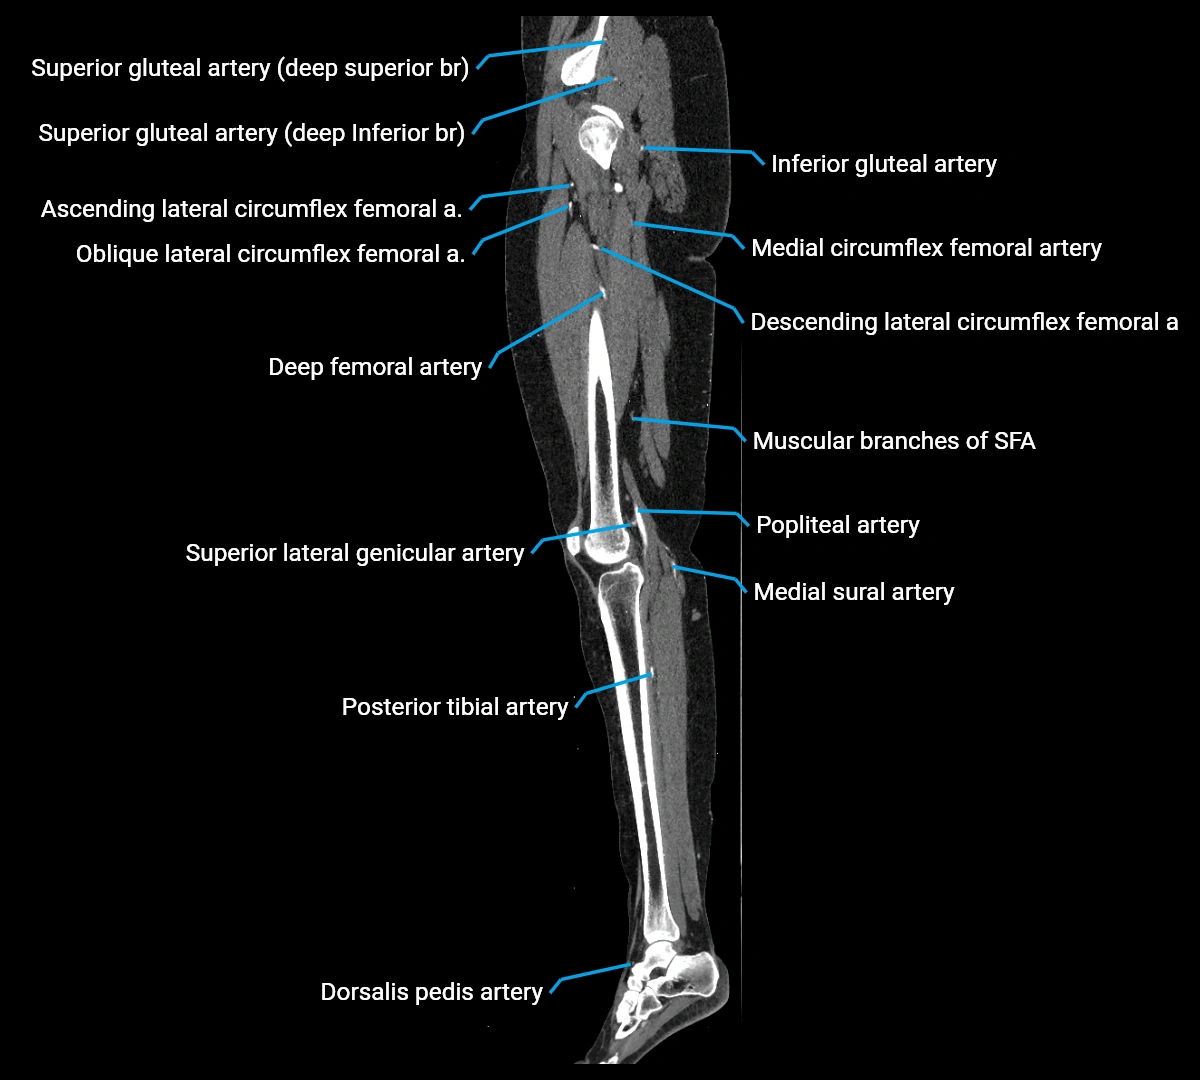

CT images

image